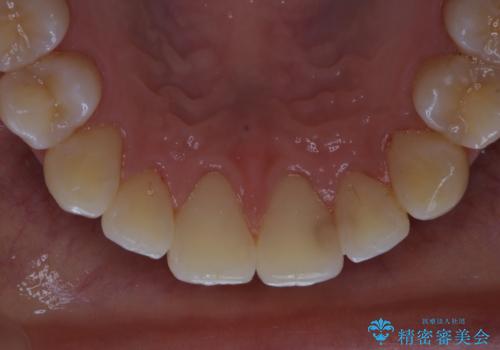

- インビザラインでのマウスピース矯正が終了したため、きれいにクリーニングして口元を明るい印象にしたいとのことでした。PMTC60分コースを行いました。

矯正治療が終わり、せっかくきれいになった歯並びも、虫歯・歯周病などになってしまっては元も子もありません。

矯正治療やセラミックなどによる被せ物の治療終了のタイミングではクリーニングを行い、汚れや着色の除去、歯と歯の間・歯と歯肉との境目などのケアをしっかりすることをおすすめしています。

ご自身での歯ブラシ・セルフケアを行うと同時に、定期的なクリーニング(PMTC)を行うことで、いつまでも健康な歯を保つことができます。